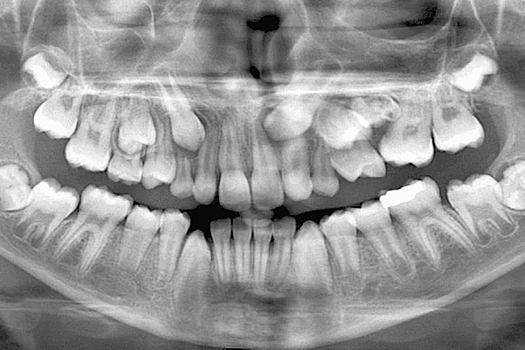

К активным исследованиям препарата ученые приступили прошлой осенью. Тогда испытания прошли на детях, у которых из-за врожденных аномалий нет зубов.

Сейчас средство хотят испытать на взрослых в возрасте 30-64 года. Ученые заявили, что под деснами скрыты зачатки третьего набора зубов. Как раз на их «пробуждение» и рассчитывают специалисты.

Исследование, проворимое с участием животных, показало, что такое возможно, если блокировать белок USAG-1. В результате ученым удалось вырастить новые зубы мышам и хорькам.

Ожидается, что новый препарат, прежде всего ориентированный на детей, может быть доступен к 2030 году.